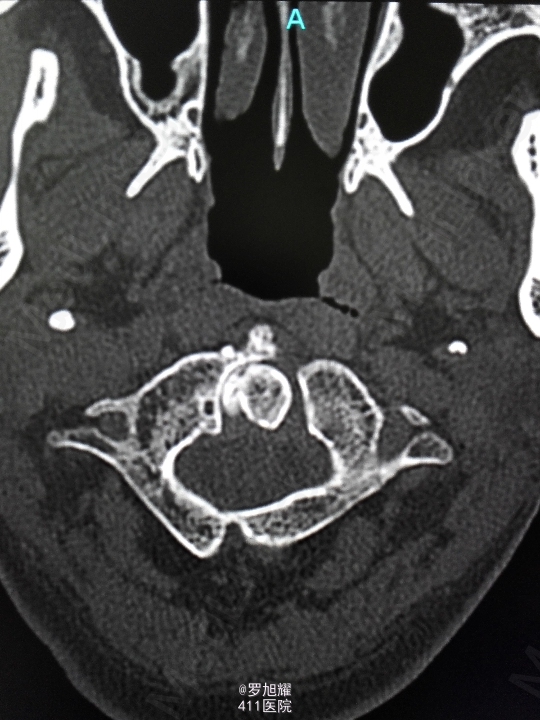

右侧躯体麻木1年,右上肢及下肢麻木2月余。 查体:颈椎活动受限,右上肢肘关节以远痛温觉减退,右侧胸4平面以下痛温觉及触觉减退,四肢肌力尚可,右侧霍夫曼征阳性,右侧上下肢所有腱反射亢进。 颈椎X线示:颈2椎板棘突缺如,颈3棘突肥大增高。 颈椎CT示:颈2椎板棘突缺如,颈3棘突肥大增高,颈2/3椎间盘突出,左侧颈2残留部分椎板进入椎管。枢椎齿突增生,寰枢关节退变。 颈椎MRI示:颈2/3椎间盘突出,左侧颈2椎板进入椎管,颈髓受压变性。

查体:颈椎活动受限,右上肢肘关节以远痛温觉减退,右侧胸4平面以下痛温觉及触觉减退,四肢肌力尚可,右侧霍夫曼征阳性,右侧上下肢所有腱反射亢进。 颈椎X线示:颈2椎板棘突缺如,颈3棘突肥大增高。 颈椎CT示:颈2椎板棘突缺如,颈3棘突肥大增高,颈2/3椎间盘突出,左侧颈2残留部分椎板进入椎管。枢椎齿突增生,寰枢关节退变。 颈椎MRI示:颈2/3椎间盘突出,左侧颈2椎板进入椎管,颈髓受压变性。